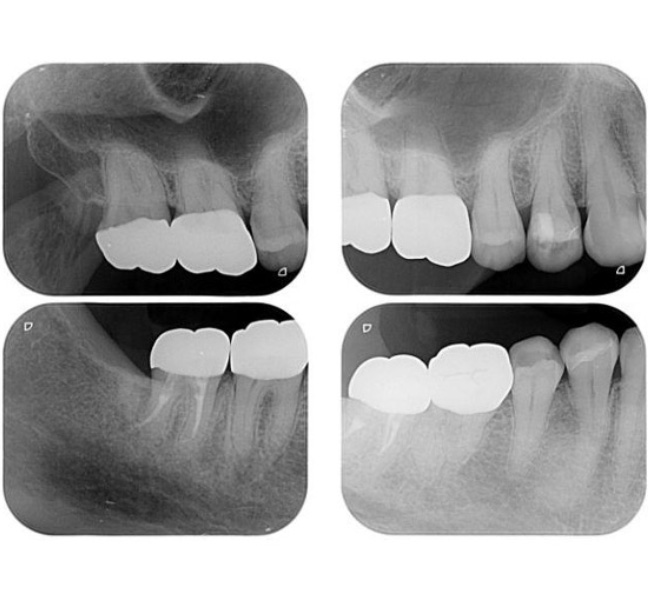

治療前

(レントゲン)

【レントゲン】左下奥歯のレントゲン所見

一番奥の歯(左下7番)は、被せ物の下の土台にヒビ(破折)が入っており、歯の内部と外部の両方から細菌感染が進んでいる「末期的な状態」です。周囲の骨が広範囲に溶け、大きな黒い影として写っています。

その手前の歯(左下6番)は、過去に根を分割する処置がされていますが、土台が根の方向からズレており、噛み合わせの強い力に耐えきれず地盤(骨)を半分以上失っています。

どちらの歯も、これ以上の補修では建物の重み(噛み合わせの力)を支えられず、放置すれば周囲の健康な骨までさらに溶かしてしまうため、将来を見据えて「戦略的な抜歯」を選択しました。